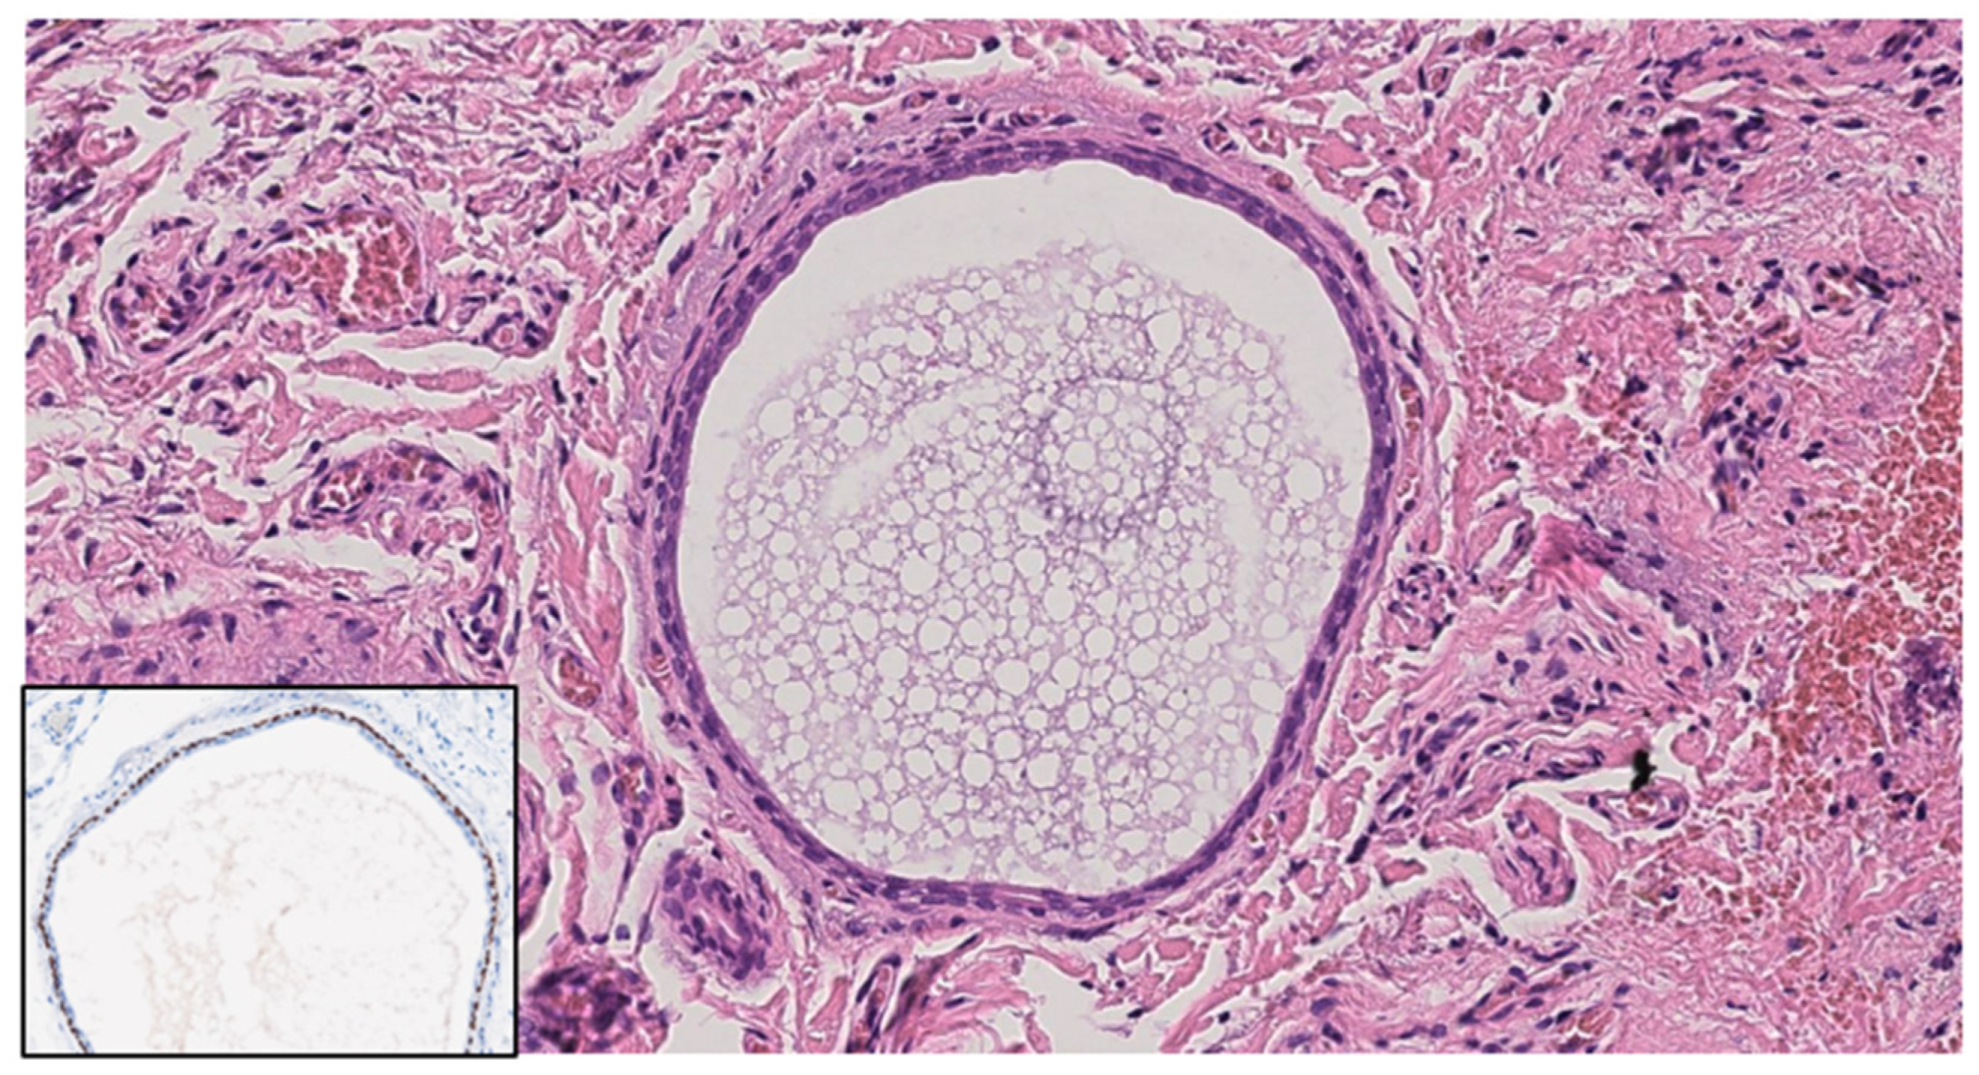

Basal cell carcinoma typically presents with distinct architectural abnormalities, branched lobules with a millefeuille pattern, clefting, and a darker rim. These characteristics are essential for the diagnosis of BCC and were absent in our hidrocystoma cases, reinforcing the benign nature of these lesions. Additionally, the lack of such features emphasizes the importance of LC-OCT in identifying the unique characteristics of hidrocystomas, thereby aiding in their differentiation from BCC. Thus, by employing LC-OCT alongside other diagnostic modalities, clinicians can achieve a more accurate diagnosis, ensuring that appropriate management strategies are implemented for both benign and malignant skin lesions. Our LC-OCT findings align with well-established histopathological characteristics of hidrocystomas, which are cystic spaces in the dermis typically lined by a dual-layered epithelium [21,30] (Figure 3).

Figure 3. Histological image. Dermal cyst is composed of an inner layer of cuboidal epithelium and an outer myoepithelial cell layer; p63 (insert) highlights myoepithelial cells. Hematoxylin and Eosin; original magnification (OM) ×20; immunohistochemistry, chromogen diaminobenzidine (insert); original magnification (OM): p63, ×20.